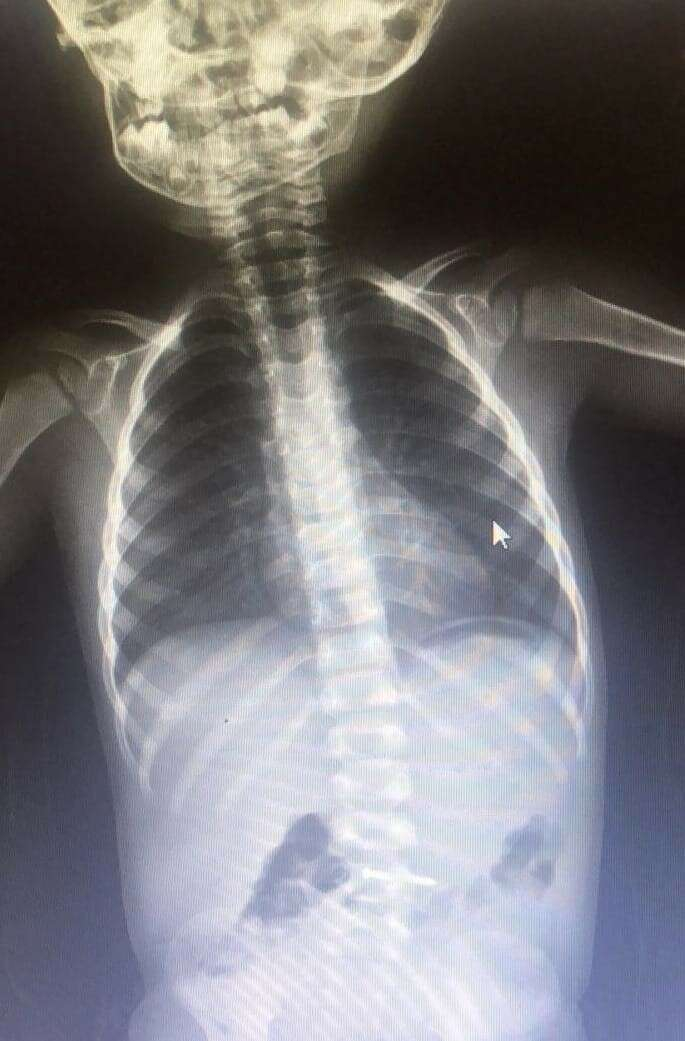

2 yaşındaki Asil K., evde oynarken yerde bulduğu çiviyi ağzına atıp yuttu.

Yapılan tetkiklerde çivinin midesinde olduğu tespit edilen çocuk, ambulansla Bursa Yüksek İhtisas Eğitim ve Araştırma Hastanesi’ne sevk edildi.